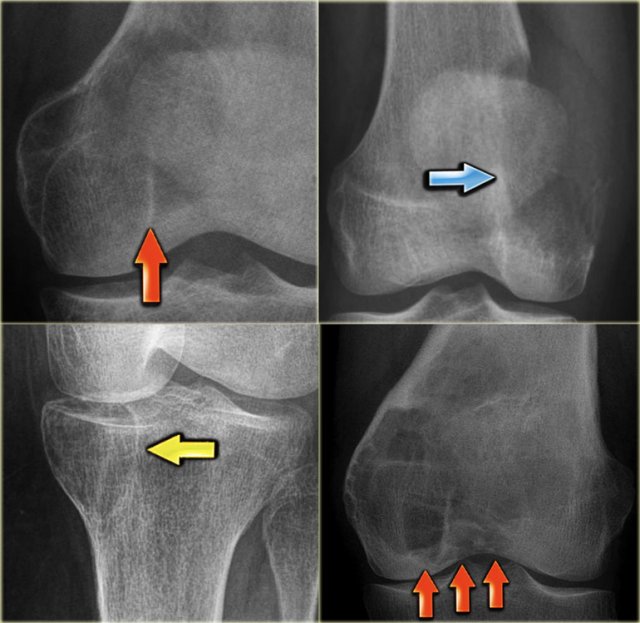

On the left more examples of GCT around the knee.

Notice that most of these lesions are well-defined and located in the epiphysis and extend into the metaphysis.

Some extend onto the articular surface (yellow arrow and small red arrows).

The lesion on the upper right has an ill-defined border with a broad zone of transition (blue arrow).

Here another typical giant cell tumor presenting as an osteolytic lesion in the epi- and metaphysis of the proximal tibia.

Non-specific intermediate signal intensity on T1WI and mixed high and low SI on T2WI with FS.

The low signal on T2WI is usually due to hemosiderin within the GCT.